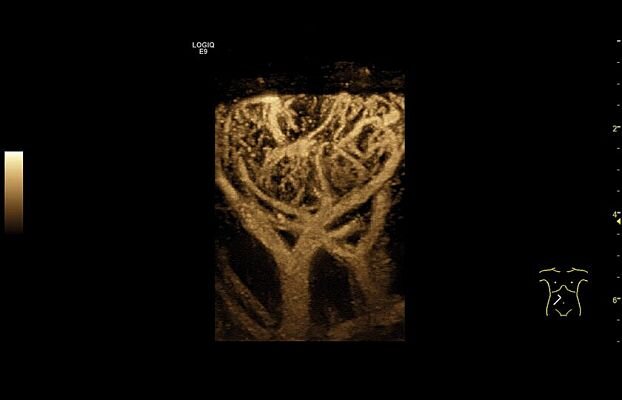

Клинические изображения

- Real Time 4D - трехмерное сканирование в режиме реального времени. Включает режим инверсии, кинопетлю 4D и 3D в режиме ЦДК.

- Real Time 4D - трехмерное сканирование в режиме реального времени. Включает режим инверсии, кинопетлю 4D и 3D в режиме ЦДК.

Исключительная универсальность и качество визуализации

Задачи, лежащие в сфере общей визуализации весьма широки, и врачам ежедневно приходится вести прием большого числа пациентов, и проводить диагностику различных заболеваний. Пациенты могут быть разного возраста, от новорожденных до престарелых, и иметь разную массу тела, в том числе избыточную. Всё это не должно быть помехой для качественной и достоверной диагностики.

LOGIQ E9 имеет невероятно широкий спектр применения, который включает исследования брюшной полости, сердечно-сосудистой системы, органов репродукции, скелетно-мышечного аппарата, малых органов и структур, мочевыделительной системы, транскраниальные исследования у взрослых и детей.

Экспертное качество визуализации системы LOGIQ E9 является основой для оперативного получения клинически важной информации, что в свою очередь необходимо при принятии обоснованных решений. Передовые функции, такие как объемная навигация, эластография компрессионная и сдвиговой волны, исследования с контрастными веществами и визуализация в режимах 3D/4D ещё больше расширяют возможности для быстрой и точной диагностики, а простой интуитивно понятный интерфейс, инструменты автоматизации и протоколы исследований позволяют максимально оптимизировать рабочий процесс и справится с самой высокой нагрузкой и большим пациентопотоком.

- B-Flow и Color B-Flow — технология прямой недопплеровской визуализации кровотока в режиме реального времени, которая позволяет получить гемодинамический профиль с повышенной чувствительностью и разрешением без нежелательных сигналов от окружающих тканей в сосудах всех типов, от крупных, например, сонной артерии, до мелких, например, сосудах паренхиматозных органов.